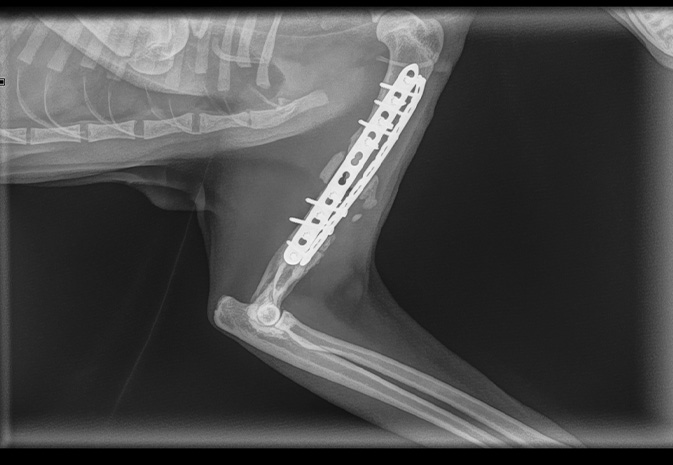

Fractures